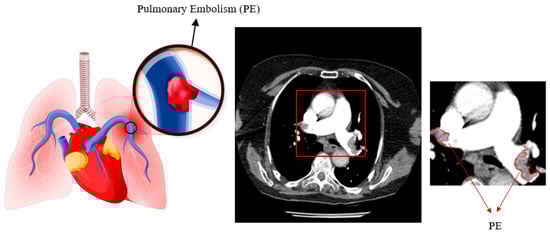

1. Introduction